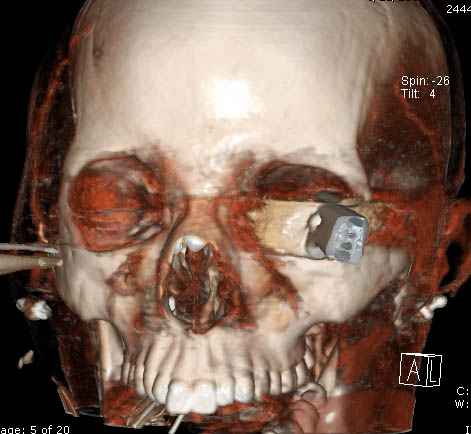

В своих выступлениях я рассказывал, что наши центры в мирное время по пенетрирующим травмам не уступает Ираку или Афганстану, и вот недавно к нам поступила больная 22 лет, травма "ножом в глаз" от бывшей подруги нынешнего "бой френда".

При поступлении в сознании, жаловалась на неприятные ощущения в глазнице.

По протоколу сделаны все необходимые исследования: рентген, ангиограмма с 3Д реконструкцией, где обнаружили что все жизненно важные сосуды не задеты, даже некоторые "сидят" изгибаясь на ноже.